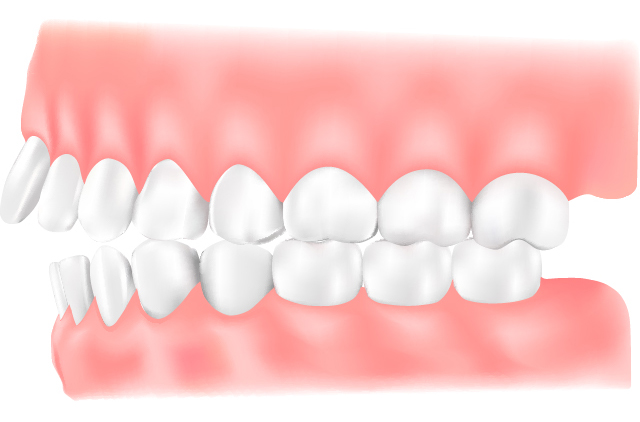

上下顎前突

上顎・下顎ともに前方へ突き出ている状態です。